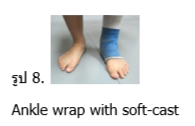

- การใส่เฝือกนุ่ม (Ankle wrap with soft-cast) (รูป 8) ผู้เขียนชอบวิธีนี้มากที่สุด